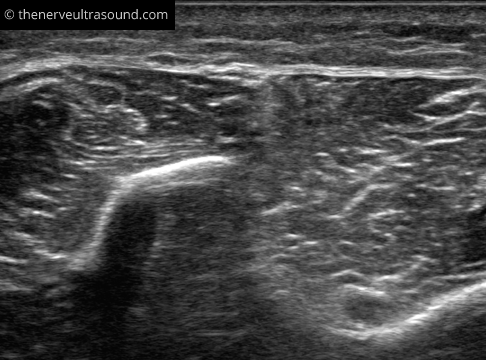

In the distal lower leg, the superficial peroneal nerve runs in the septum between the peroneal muscles and the extensor digitorum longus muscle to reach a superficial position. To find the superficial peroneus nerve at this position look for the anterior border of the fibula bone “pointing” with the intermuscular septum to the nerve at its superficial posion.

In the same section the deep peroneal nerve may be seen in the depth near the anterior tibial artery.